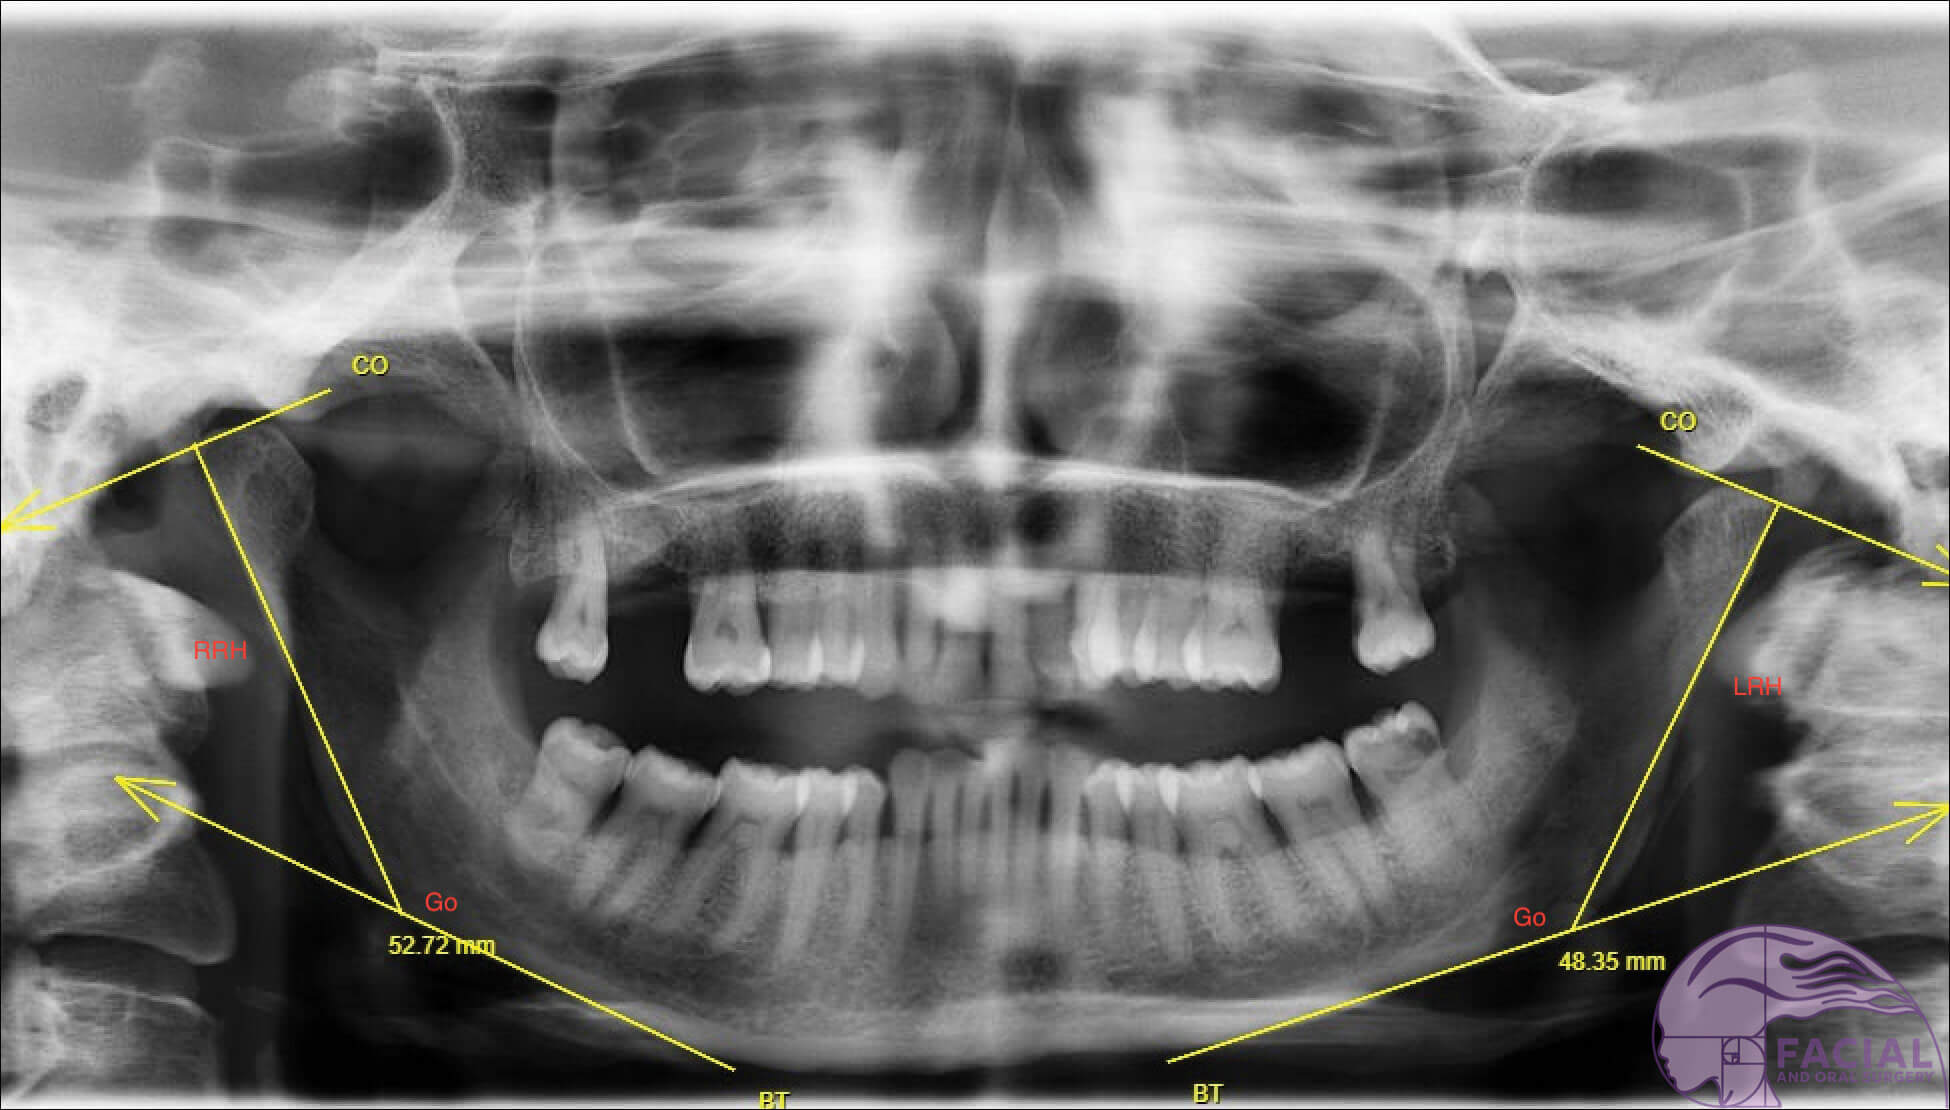

Figure 2b: Case 2 Orthopantomagram: Roll dominant mandibular asymmetry with no chin midline deviation.

Right ramus height (RRH). Left ramus height (LRH).

Positive asymmetry index (AI) values indicate that the right mandibular ramus is longer; a negative AI indicate an elongated left side. The AI [14] to evaluate the severity of asymmetry between heights of both sides of the ramus of the mandible:

AI, % = RRH - LRH / RRH + LRH × 100%

- Diagnosis: Parry-Romberg Syndrome (i.e. Left hemifacial atrophy) affecting left side of mandible and soft tissues including muscle and fat. The left ramus height is 5mm shorter compared to the normal right side but no disocclusion due to dental compensation by over-eruption of teeth on left side. Roll-dominant asymmetry (see Figure 2b).